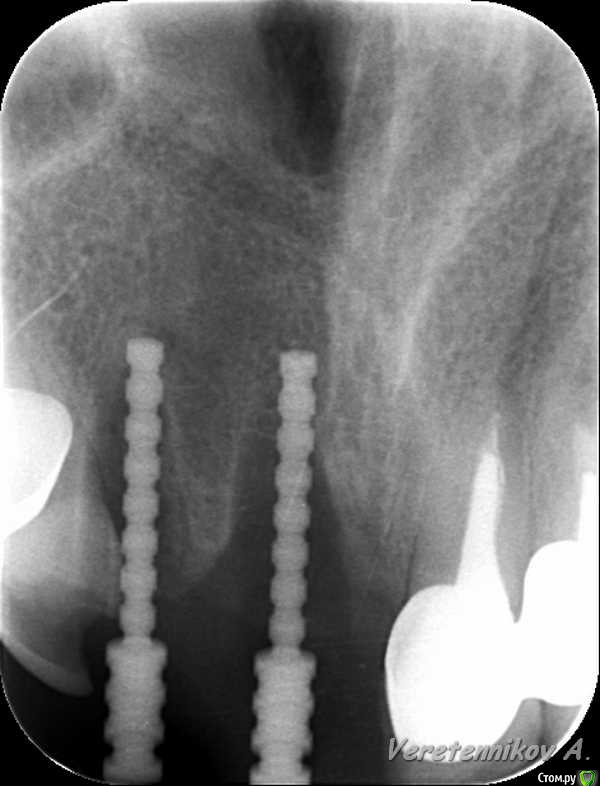

an_ver Опубликовано 26 марта, 2015 Поделиться Опубликовано 26 марта, 2015 (изменено) 11,12..11 трещина корня,вест.часть,12 рыхло все..сгнило.Убрал,кюретаж,11 вест. стенки нет на 2/3.Установил 11-4,2*13;12-3,75*13 мм..все Альфа.Мп3,мембрана эволюшн.11 заглушил,12-временный абатмент,коронка.Шил викрил 4,0. Фсе...пинайте Изменено 26 марта, 2015 пользователем an_ver 7 Ссылка на комментарий

колесников Опубликовано 26 марта, 2015 Поделиться Опубликовано 26 марта, 2015 Дело вкуса ,но я бы взял 11,5мм и 11ый поглубже поставил. Был неприятный опыт с длинными имплантами во фронте. Толи из-за анатомии ,то-ли из-за плеча, но получалась окончатая резорбция в области алекса импланта. Ссылка на комментарий

an_ver Опубликовано 27 марта, 2015 Автор Поделиться Опубликовано 27 марта, 2015 Дело вкуса ,но я бы взял 11,5мм и 11ый поглубже поставил. Был неприятный опыт с длинными имплантами во фронте. Толи из-за анатомии ,то-ли из-за плеча, но получалась окончатая резорбция в области алекса импланта.У меня такая мысль была...но стабилизация блин))...тут и так ниже ЦЭС на 3 мм Ссылка на комментарий